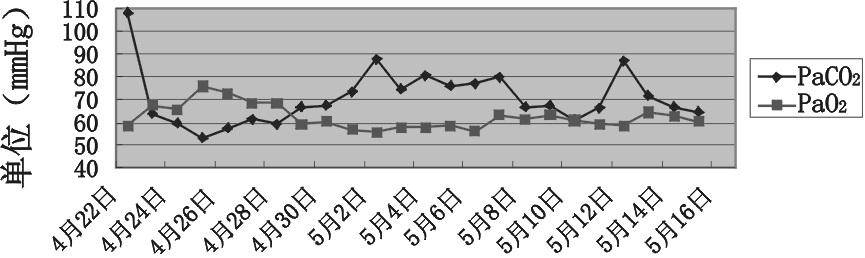

5月8日调整为加温湿化高流量鼻导管吸氧(heated humidified high flow nasal cannular,HHFNC),湿化温度37℃,流量35 L/min,氧浓度30%~35%,监测PaCO2波动于65 mmHg左右,PaO2波动于60 mmHg左右。5月12 日欲转科,更换为低流量鼻导管吸氧(2 L/min),患者再次出现嗜睡,复查PaCO2 85 mmHg,再次给予HHFNC后复查PaCO2 60 mHg~70 mmHg。患者住院期间PaCO2及PaO2变化曲线见图 2。

| 图 2 患者住院期间PaCO2及PaO2变化曲线 |

HHFNC在本例患者撤机拔管后的应用充分显示其有效性,可能与下列因素相关:(1)加温及湿化:生理状态下,吸入气体经鼻咽部、气管、支气管等部位的逐级加温、湿化,到达肺泡时被加温到体温状态(37 ℃)、相对湿度100%、绝对湿度44 mg/L,在此状态下气道上皮细胞处于最佳黏液纤毛转运状态,气道内分泌物保持良好的水化状态,便于吸出或咳出。HHFNC所提供的气体可达到体温饱和湿度,促进痰液引流,有利于感染控制。(2)HHFNC能够提供气道正压,提高患者的动脉血氧饱和度及氧合指数,闭嘴呼吸能进一步改善上述指标,而气道正压水平与流量呈正相关;HHFNC能减少解剖死腔,增加肺泡通气量,从而降低动脉血二氧化碳分压水平;HHFNC能够降低呼吸频率,减少呼吸功耗,降低患者无创及有创机械通气的机率。(3)与机械通气相比,呼吸衰竭患者对HHFNC的适应性更好,减少氧疗的中断,改善治疗效果。本例患者在撤机拔管采取鼻导管吸氧后再次出现嗜睡,应用HHFNC后动脉血二氧化碳分压水平显著下降,氧合指数明显增加,提示HHFNC在降低成功脱离有创机械通气后再次气管插管机率方面有重要意义。其原理与上述因素有关,但部分结论仍存在一定争议,同时性别、体位等对HHFNC效果的影响至今尚无定论。